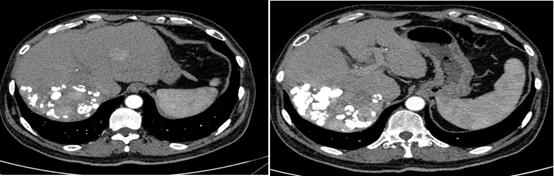

2018-12-11腹部CT检查提示,肝硬化、脾略大、门静脉高压;肝S6占位性病变,考虑原发性肝癌;肝S7段2枚结节;肝多发小囊肿,肝右叶钙化灶;双肾囊肿。

图片

图:腹部CT检查(2018-12-11)